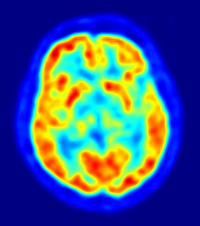

La stimulation cérébrale profonde pourrait aider à freiner le déclin des fonctions cognitives et de la mémoire. La méthode est relativement simple : il s’agit d’envoyer un courant électrique dans une partie du cerveau, à l’aide d’une électrode.

La technique a déjà été expérimentée avec succès pour la maladie de Parkinson. En effet, les neurochirurgiens ont constaté que les patients ne tremblaient plus lorsque l’électrode était posée dans leur cerveau.

C’est le Professeur Lozano et son équipe Canadienne qui ont découvert de manière fortuite les potentiels de la stimulation cérébrale profonde dans la maladie d’Alzheimer. Ils cherchaient initialement à réveiller chez une personne obèse le sentiment de satiété, stimulant l’hypothalamus (structure du système nerveux central). À leur grand étonnement, le patient a raconté avec précision le souvenir d’une scène survenue trente ans auparavant.